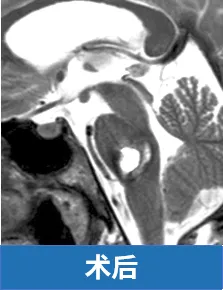

最终手术顺利,术后一年,Laura笑着进到诊室复查,明显可以看到她的面神经和外展神经功能已基本恢复。“我很感恩现在的一切,我能帮孩子梳头发,还能自己做饭。”Laura说着,抬手捋了捋头发,脸上的笑容自然又轻松。她的复查影像显示:脑桥区域没有残留病灶。